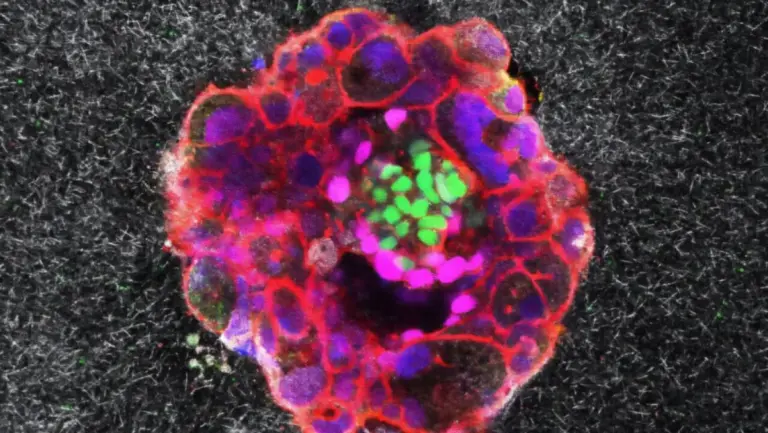

Gezondheid en ziekte bij ongeboren kinderen voorspellen is niets nieuws, zeker met de moderne technologie in 2025. Maar het inschatten van het IQ van een foetus? Dat klinkt als pure sciencefiction. Toch beweert een Amerikaans bedrijf genaamd Heliospect Genomics dit nu mogelijk te maken.

Heliospect Genomics, gevestigd in Californië, biedt welgestelde ouders de kans om voor tienduizenden euro’s embryo’s genetisch te laten ‘screenen’ op hun potentiële intelligentie. Volgens een recent onderzoek in een Britse krant zouden zij hiermee een flinke slag slaan op de groeiende markt van ‘designerbaby’s’.

Maar werkt de techniek eigenlijk wel zoals Heliospect het belooft? De wetenschap weet inmiddels dat intelligentie weliswaar deels genetisch bepaald is, maar er bestaat geen simpel aan- of uit-gen voor slimheid. Het IQ is ontworpen uit een complexe cocktail van tientallen overlappende genen én natuurlijk beïnvloed door de sociale omgeving. Bovendien is ‘intelligentie’ wetenschappelijk gezien nog altijd een lastig meetbaar begrip. En los van deze technische haken en ogen: er zijn stevige ethische bedenkingen.

Desondanks wijst het onderzoek uit dat Heliospect haar diensten nu aanbiedt aan rijke cliënten die IVF-behandelingen ondergaan. De kosten: meer dan 50.000 dollar voor het testen van 100 embryo’s. En naar eigen zeggen: “De eerste baby’s zijn inmiddels onderweg”.